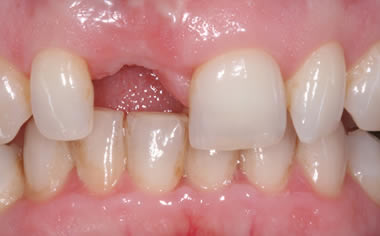

Before & After Gallery

More front teeth replaced by dental implants

Case Four (6 images)